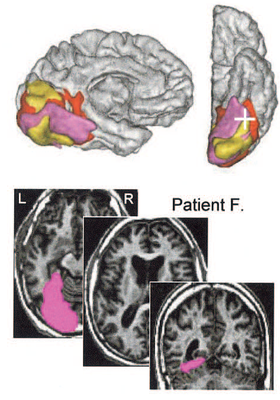

RECONNAISSANCE VISUELLE DES MOTS ET PLASTICITE CEREBRALE

Ressources reconnaissance visuelle des mots

Image1.png